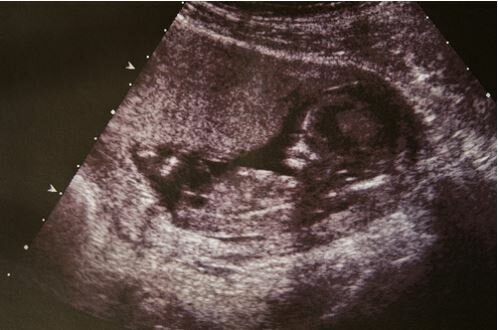

„V posledních měsících jsme s manželkou věděli, že očekáváme velmi nemocné dítě. Náš syn měl trpět vážnou formou hydrocefalu. Syn měl zkrátka mít přebytečnou mozkomíšní tekutinu. Názory ostatních lékařů potvrdily počáteční diagnózu. Slyšeli jsme také, že existuje 90% pravděpodobnost, že syn zemře brzy po porodu. Lékaři nám řekli, jak by vypadala možná péče o dítě se zhoršenou funkcí života. Zažili jsme něco, co nelze popsat slovy. “

Charlie Edward Schnarr se narodil bez hydrocefalu! Lékaři nedokázali vysvětlit tento jev, protože všechny studie potvrdily jejich závěry. To však neznamená, že chlapec je zcela zdravý.

Malý Charlie má hypertrofické srdeční komory, ale naštěstí to jeho život neohrožuje. Čas od času se musí podrobit rutinním testům.